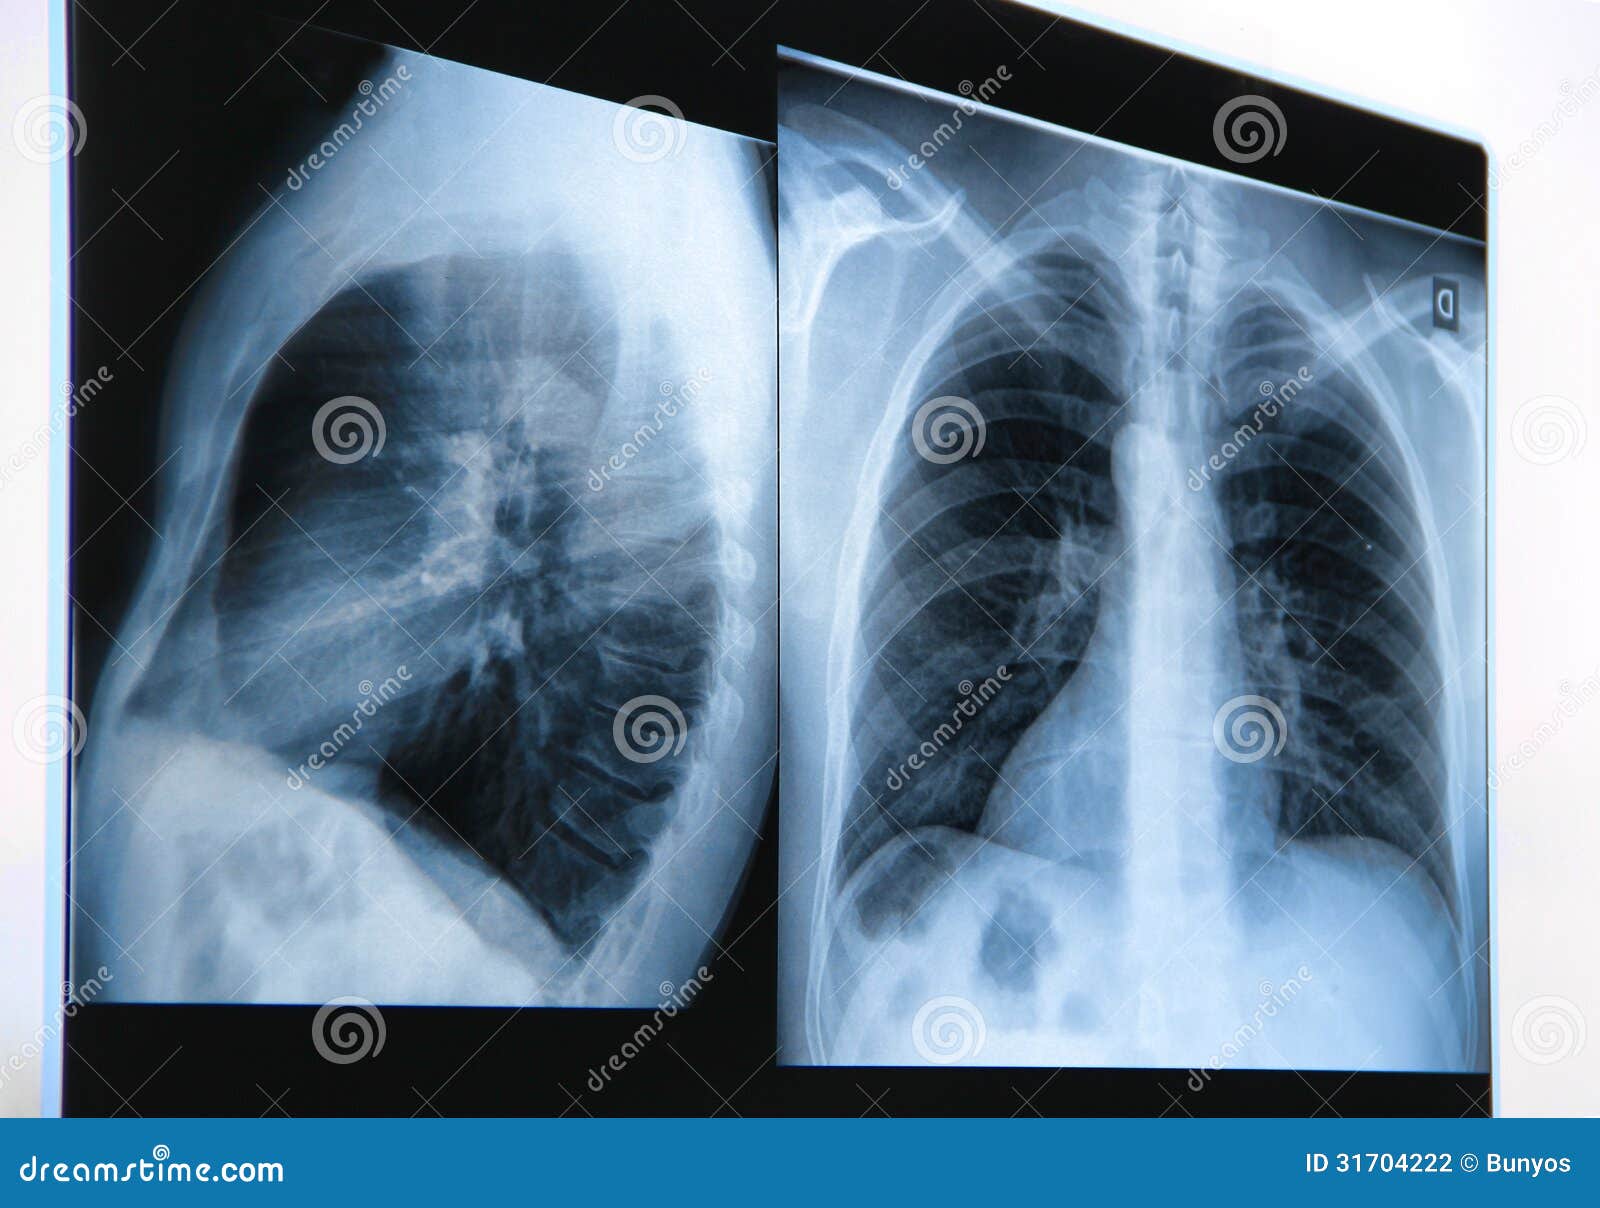

Premium Photo A chest xray shows a chest xray.

Premium Photo A chest xray shows a chest xray. Does A Chest Xray Show If You Smoke Smoking can lead to hyperinflation of the lungs (copd) and other patterns consistent. Smoking can change the physical appearance of the lungs. If someone has been smoking a long time and/or heavily, there are changes in the interstitial markings (all the little white. Does A Chest Xray Show If You Smoke.

Premium Photo A chest xray shows a chest xray. Does A Chest Xray Show If You Smoke Smoking can lead to hyperinflation of the lungs (copd) and other patterns consistent. If someone has been smoking a long time and/or heavily, there are changes in the interstitial markings (all the little white. Smoking can change the physical appearance of the lungs. Does A Chest Xray Show If You Smoke.